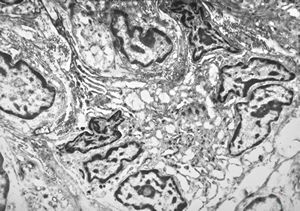

F,41y. | synovial metaplasia - capsule of implantate

F,41y. | synovial metaplasia - capsule of implantate

F,41y. | synovial metaplasia - capsule of implantate

F,41y. | synovial metaplasia - capsule of implantate

F,41y. | synovial metaplasia - capsule of implantate

F,41y. | synovial metaplasia - capsule of implantate

F,41y. | synovial metaplasia - capsule of implantate

F,41y. | synovial metaplasia - capsule of implantate

F,41y. | synovial metaplasia - capsule of implantate